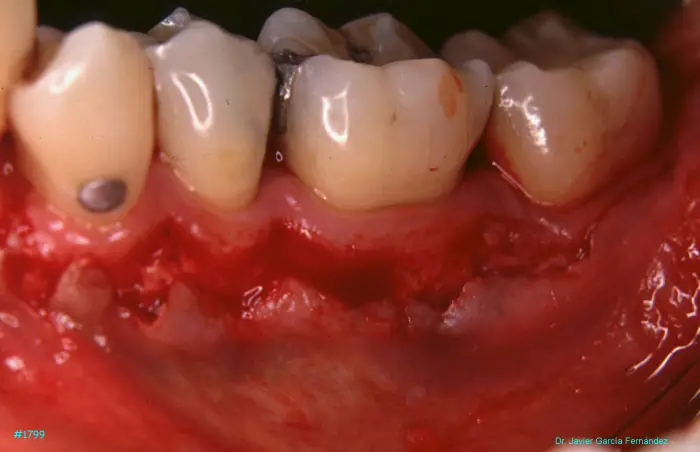

image 65